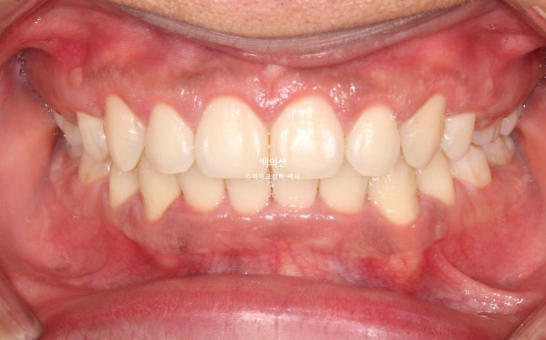

그리고 25년 5월, 본원에서 교정치료를 이어 시작한지 1년 10개월만에 치료를 마무리 했습니다.

클리피씨 브라켓을 뗀 후 잇몸성형 직후 사진입니다.

앞니 각도와 어금니 교합은 좋고 1급 교합관계를 보입니다.

잇몸성형 일주일 후 잇몸이 잘 아물었습니다.